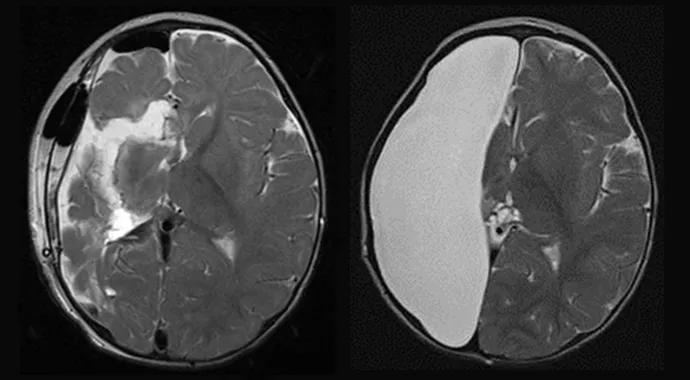

Moosa-Bingaman-Fig2

Figure 2. Illustrative case to highlight the misleading postoperative EEG after functional hemispherectomy. A 2-year-old boy presented with spasms and generalized tonic seizures. EEG showed generalized hypsarrhythmia, and MRI brain scan showed encephalomalacia due to remote right middle cerebral artery ischemia. Patient had recurrence of postoperative seizures soon after functional hemispherectomy. EEG showed ictal patterns on the unoperated hemisphere. Patient became completely seizure-free after conversion to anatomic hemispherectomy. EEG at six months after surgery showed normal background in the opposite hemisphere and diffuse attenuation over the right hemisphere, as expected after anatomic hemispherectomy.